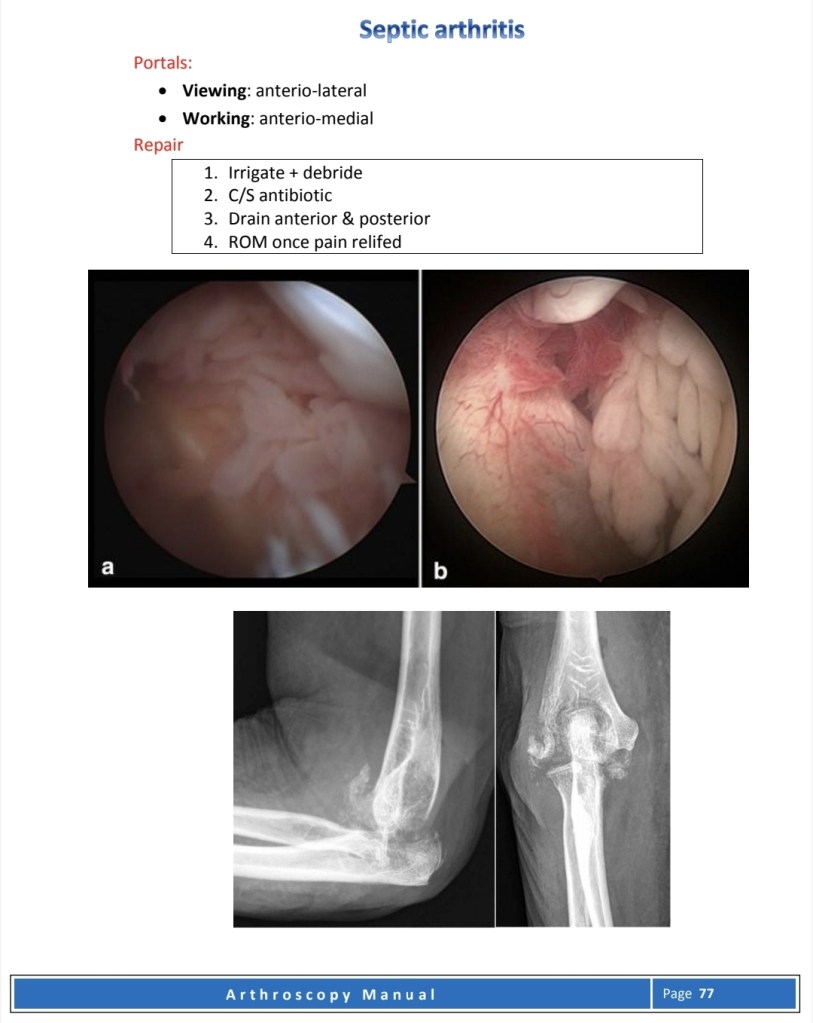

Other Elbow problems

Elbow procedures